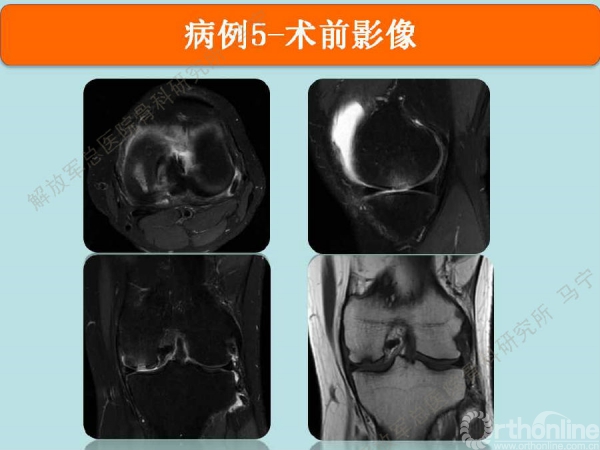

病例5

陈某,男,31岁,足球训练伤。

术中显示损伤部位及第四代组织工程软骨修补术后。术后三个月核磁显示组织工程软骨具备一定厚度,胶原含水量接近正常,还存在GAP现象。随访还在进行中。